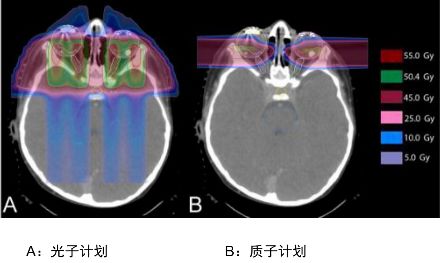

儿童头颈部肿瘤

这是头颈部肿瘤剂量分布图比较,我们明显能看到两者的差异,常规放疗蓝色区域很大,说明射线对病灶周边的正常组织有不可避免的损害,质子放疗可以减少咽喉和口腔部位的放疗损伤,降低发生口角炎、口腔炎、吞咽困难、口干的发生率。